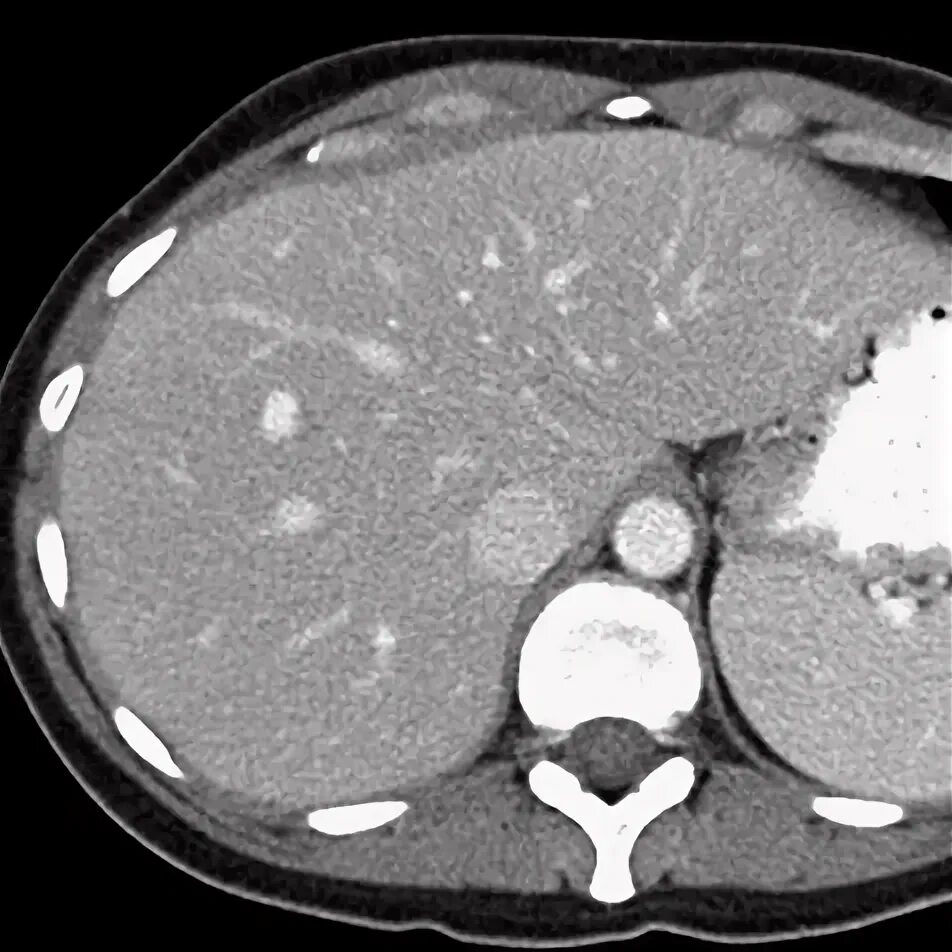

Образования печени кт